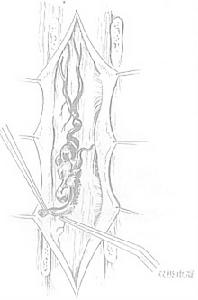

2、ⅡⅢ型診斷髓內動靜脈畸形病灶可通過T1加權像上的流空徵象加以識別。在T2加權像上常並有脊髓內出現異常信號,脊髓周圍的流空徵象提示脊髓病變周圍的部分。脊髓動脈造影在確定髓內病變上是必要的,但在區分Ⅱ型和Ⅲ型病變上並不總是有幫助。選擇性主動脈插管以及椎動脈、頸動脈和髂腰血管的插管造影在確定髓內病變供應的滋養動脈上是有必要的。背側和腹側的根血管經脊髓前動脈和脊髓後動脈分支供應動靜脈畸形。脊髓前動脈可能終止於髓內動靜脈畸形,或仍可能作為一段血管,可以確定脊髓動脈瘤和靜脈曲張。

3、Ⅳ型診斷磁共振成像有時顯示大的脊髓周圍的流空徵象主要表現為擴張明顯的硬膜內靜脈回流,這些畸形常常出現在胸腰連線處圓錐附近和馬尾近端。選擇性血管造影可顯示脊髓前動脈到動靜脈瘺的分布和回流靜脈。